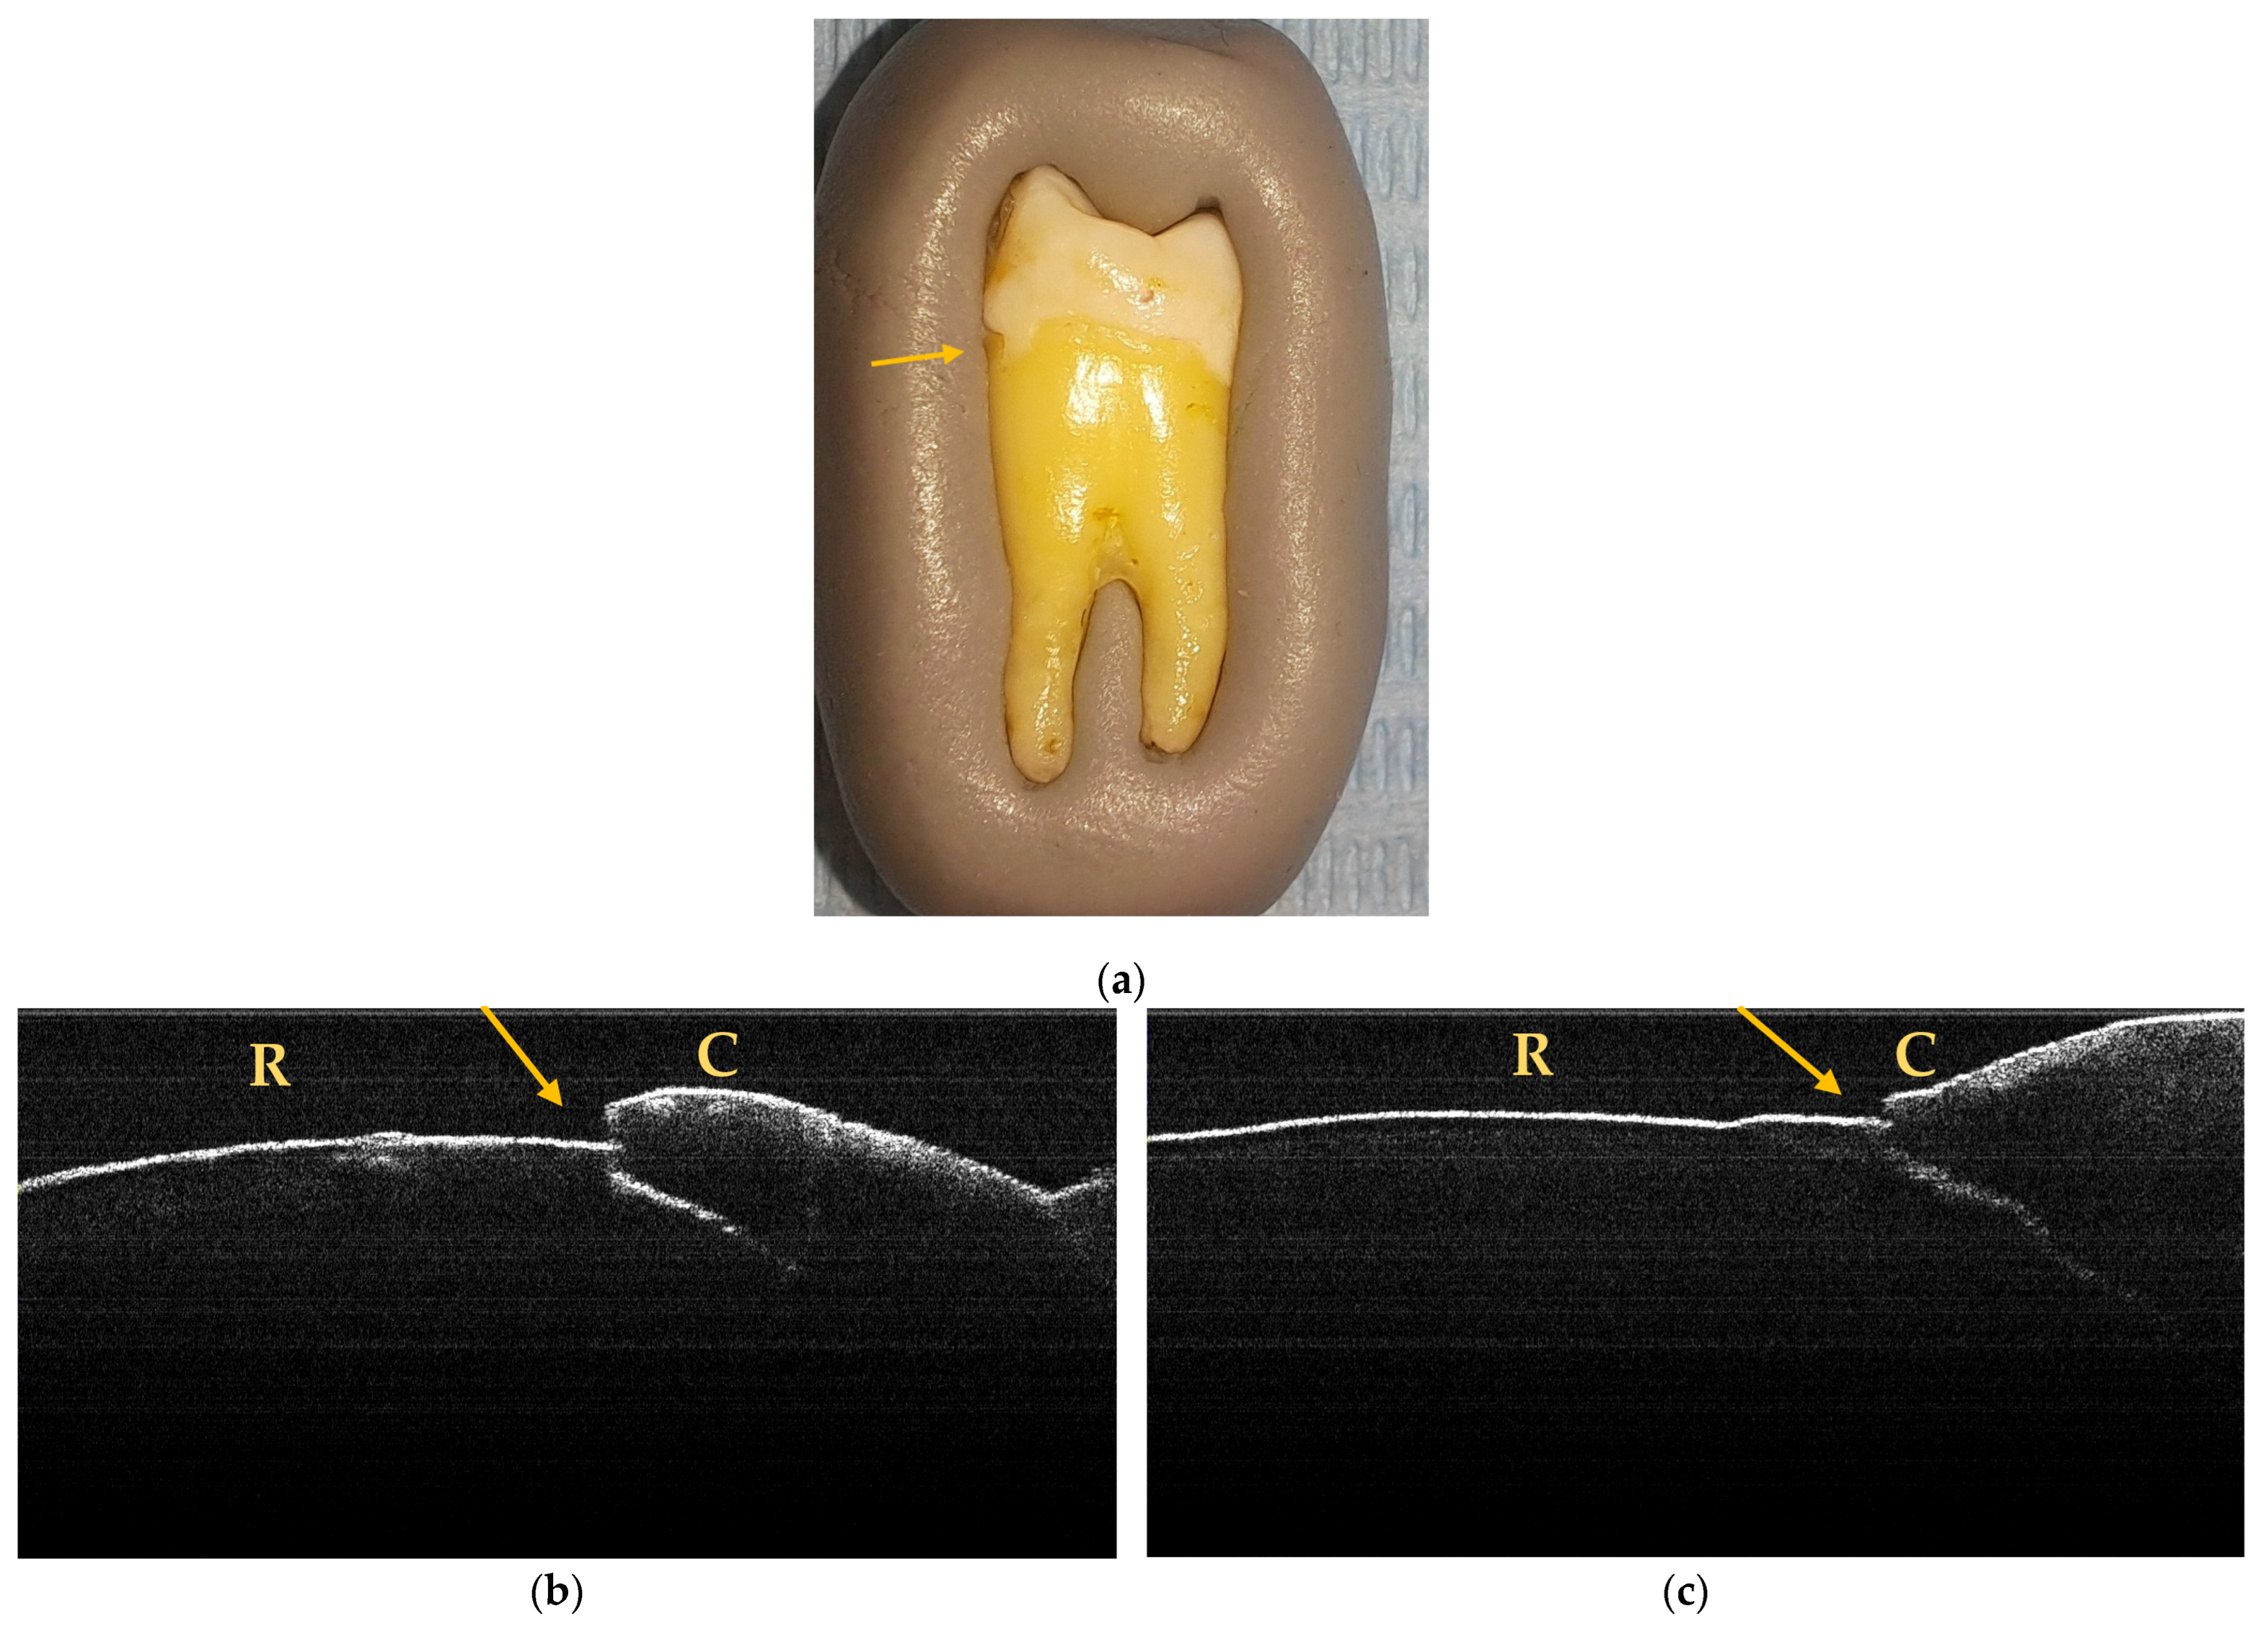

3.2. OCT Examination of Teeth Included in the Study